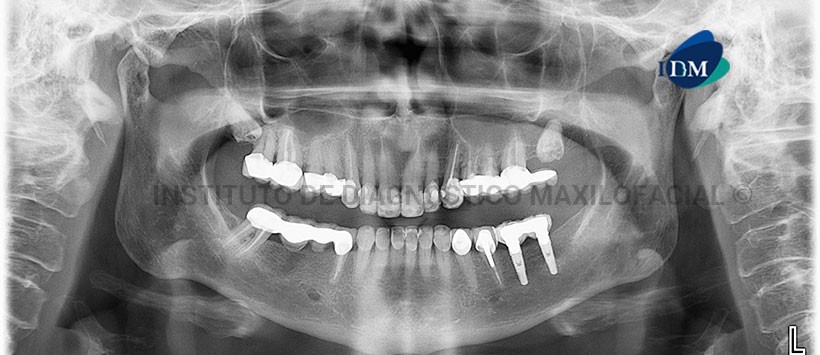

En la radiografía panorámica (Figura 1) se aprecia una imagen radiolúcida de límites definidos proyectado a nivel del tercio medio , apical interradicular de piezas 1.1 y 2.1; se aprecia además facetamiento de los contornos condilares, las piezas 18 y 28, retenidas en posición mesioangular con lesión de caries, implantes y prótesis sobre implantes en zonas de piezas 37 y 36.